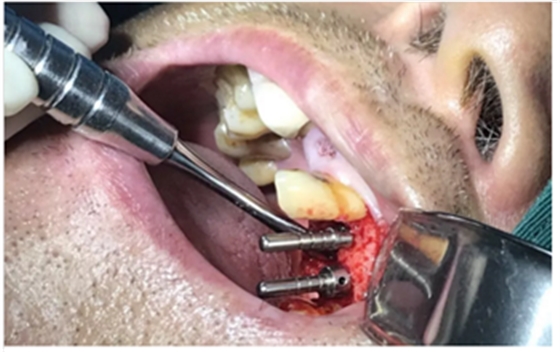

使用種植導(dǎo)板專(zhuān)用手術(shù)器械完成種植位點(diǎn)逐級(jí)備洞

進(jìn)行精準(zhǔn)測(cè)量

植體置入